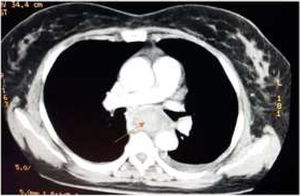

Caso clínicoPaciente femenino de 58 años, procedente de Supatá, Cundinamarca, ama de casa, sin antecedentes patológicos ni quirúrgicos de relevancia. Ingresó al hospital de tercer nivel por un cuadro de 6 días de evolución de disfagia secundaria a ingesta de cuerpo extraño (espina de pescado). En esa institución realizan una endoscopia de vías digestivas altas, que evidencia un cuerpo extraño a 25cm de la arcada dentaria, y realizan manejo mediante avance de este hasta cámara gástrica con posterior egreso hospitalario. Reingresa por episodio de dolor toracoabdominal, elevación de las cifras tensionales, hematemesis y melenas. Realizan toma de hemograma, donde se evidencia leucocitosis y anemia severa con requerimiento de transfusión de 2UI de glóbulos rojos; toman TAC de tórax, que mostró colección mediastinal en el tercio medial y distal esofágico con colección de aproximadamente 2cm con imagen de gas en su interior, compatible con absceso, además de alteración del contorno aórtico a la altura de la carina, sospechosa de lesión del espacio intramural o hematoma localizado (figs. 1 y 2), por lo que consideran perforación con lesión de aorta adyacente y remiten a nuestra institución para manejo por Cirugía Cardiovascular.